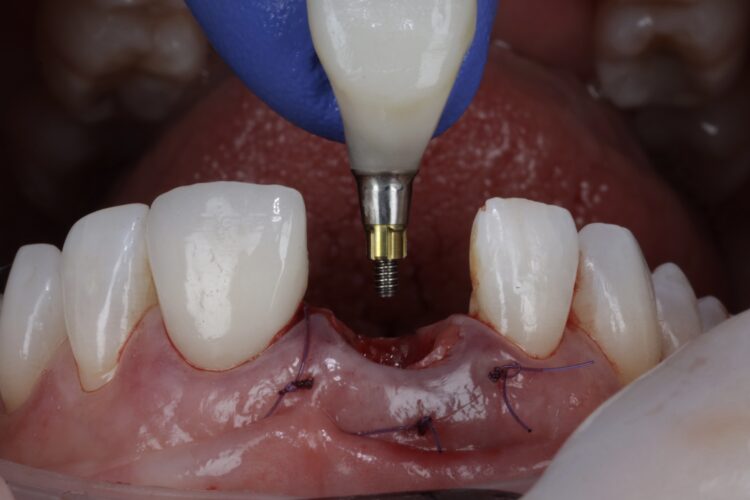

The CONELOG® Progressive-line implant maximised primary stability and in this case the implant was inserted at 70Ncm. The pre-made temporary was used as the temporary restoration; however, there would also be the option of modifying the existing crown.

The implant was placed in close contact with the palatal bone, 1mm below the buccal bone height. A temporary cylinder abutment was connected, with flowable composite placed to attach the temporary restoration. The composite resin was used to create the optimal emergence profile ensuring a highly polished restoration in the transition zone.

The temporary restoration was then reintroduced and the surgical site closed tension-free. Vertical sling sutures were placed through both papillary areas over the contact points to hold the tissue up, create a prosthetic sealand to combat natural shrinkage.